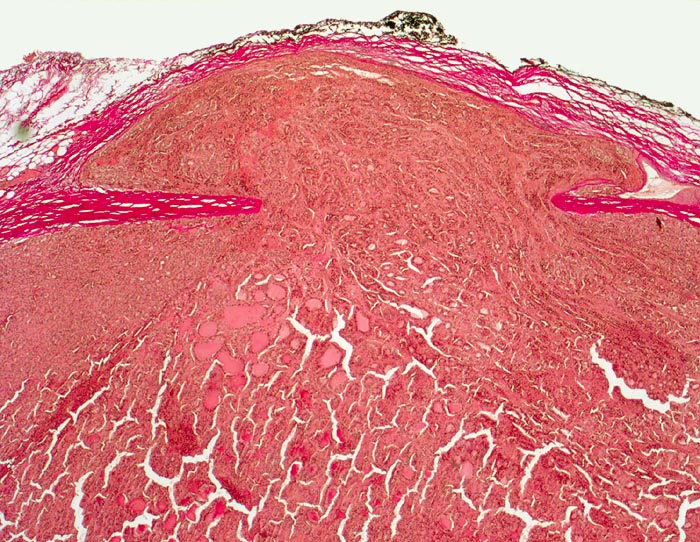

Follikuläres Schilddrüsenkarzinom: Kapseldurchbruch

Follikulärer Tumor mit dicker Kapsel. Der Tumorknoten ist zwar von einer Neokapsel bedeckt, hat aber eine imaginäre Linie entlang der ursprünglichen Kapsel überschritten.

Vor einem Jahr Schilddrüsenteilresektion wegen follikulärem Karzinom. Jetzt Resthyreoidektomie wegen Rezidiv.

Histologie

25